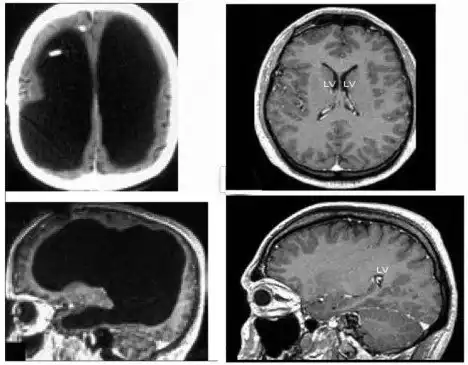

На изображении: слева МРТ Матье, справа для примера, МРТ нормального головного мозга

В возрасте 44 лет Матье обратился в клинику города Марселя с болями невыясненного генеза левой нижней конечности. Но врачи не смогли обнаружить причину болей и было принято решение всестороннего обследования организма. И вот тогда настал черед удивления медицинской общественности, потому что при КТ-сканировании головного мозга выяснилось, что он отсутствует на 75-80% от нормального объема для взрослого человека. При дальнейшем МРТ исследовании эти данные подтвердились. Причем если бы Матье не беспокоили боли в ноге, ни он, ни его окружающие ничего бы и не знали об этом удивительном феномене.